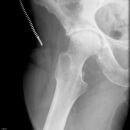

HüftTEP Luxation

Schlecht festgeschraubt